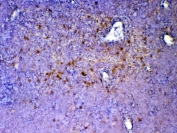

IHC testing of FFPE rat spleen tissue with ICOS antibody at 1ug/ml. Required HIER: steam section in pH6 citrate buffer for 20 min and allow to cool prior to testing.